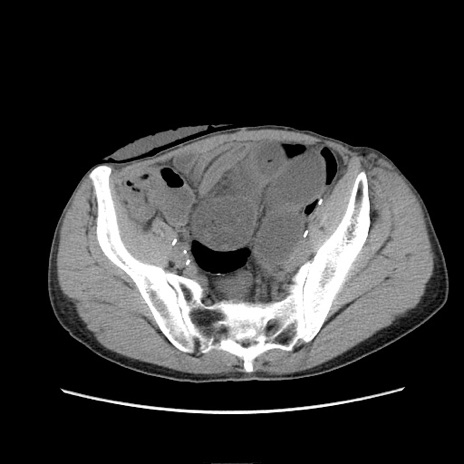

症例11(横断像)

【症例】 60歳代男性

【主訴】 下腹部痛

【現病歴】 本日夜中より下腹部痛の症状認め、受診。

【既往歴】 膀胱癌(膀胱全摘+尿管皮膚瘻術) 、胃癌術後

【身体所見】 BT 35.3℃、PR 58/min、BP 136/98mHg、腹部平坦、軟、腸蠕動音±、ストマ留置あり、左上腹部~正中部に圧痛あり、反跳痛なし。

【データ】WBC 5100、CRP0.01